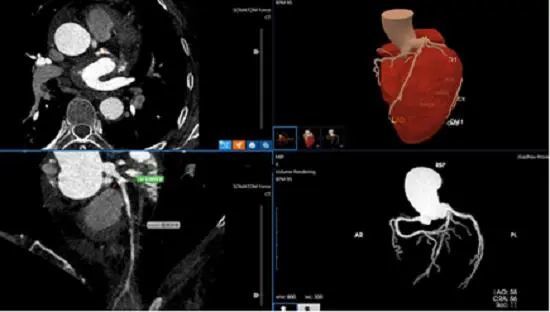

6月21日,筆者從貴州省人民醫(yī)院獲悉,該院醫(yī)學(xué)影像科診斷醫(yī)生近日運(yùn)用人工智能醫(yī)療技術(shù)僅用5分鐘,就為一名左前降支重度狹窄患者作出準(zhǔn)確診斷,經(jīng)人工智能輔助診斷冠心病技術(shù)快速準(zhǔn)確診斷為冠心病。確診后,在貴州省人民醫(yī)院心內(nèi)科施行冠狀動(dòng)脈介入治療后,目前該患者術(shù)后恢復(fù)良好。